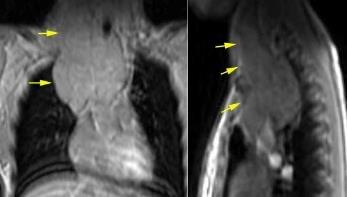

Fenómeno compensatorio por función insuficiente de médula ósea.

Mielofibrosis. Policitemia vera. Leucemia Linfoma.

Post-irradiación de médula ósea. Anemias hemolíticas. esp. Talasemia intermedia/ minor)

Haidar R. Paraspinal extramedullary hematopoiesis in patients with thalasemia intermedia. Eur Spine 2010

Lesiones inactivas “viejas”: alta intensidad de señal en T1 y T2. (infiltración grasa) Depósito de hierro: Baja intensidad de señal en T1 y T2

RM: Hipo intensidad de señal. Hemosiderosis secundaria. ¡Hígado! Haidar R. Paraspinal extramedullary hematopoiesis in patients with thalasemia intermedia. Eur Spine 2010